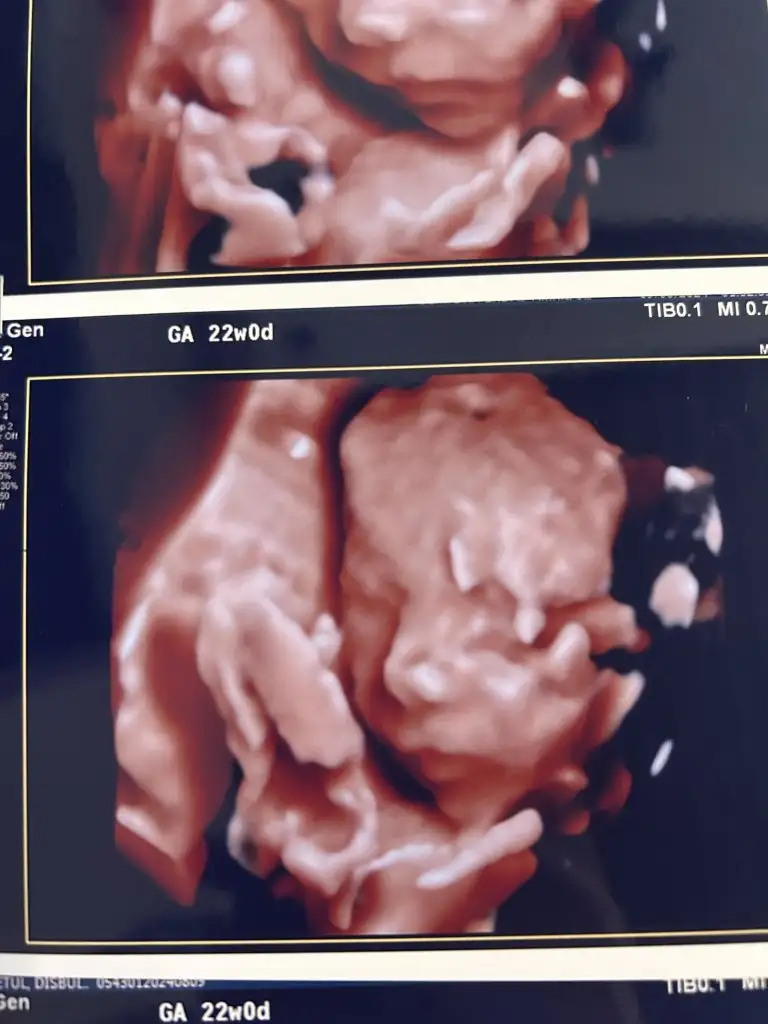

Ay kız maşallah ne kadar belirgin hatları 🧿❤ dik burunlu maşallah 🧿 benimki çok minnak kaldı seninkinin yanında. Seninki kaç haftalık oldu kuzum. Benim 20. Hafta ilk 3 boyutlu ultrason görüntümüz bu ❤🧿🧿🧿

Oyy yerim 😍🧿 Yoo seninki de gayet belirgin kuzum içerisi vıcık vıcık olduğu için ultrason görüntüsünde böyle oluyor işte ya yoksa belirginler bence hep 🥰🫠🙏 22+0 bizimki. Ultrason 22+4 falan çıktı hatta. Yarım kilo geldi ağırlığı. İki hafta sonra seninki de çok daha netleşir 🥰

Oyy yarım kilo 😍🧿 benimki 340 gram 😍❤ ay bugünleri de gördük çok şükür yaa. Aynen netleşir bir sonraki kontrole